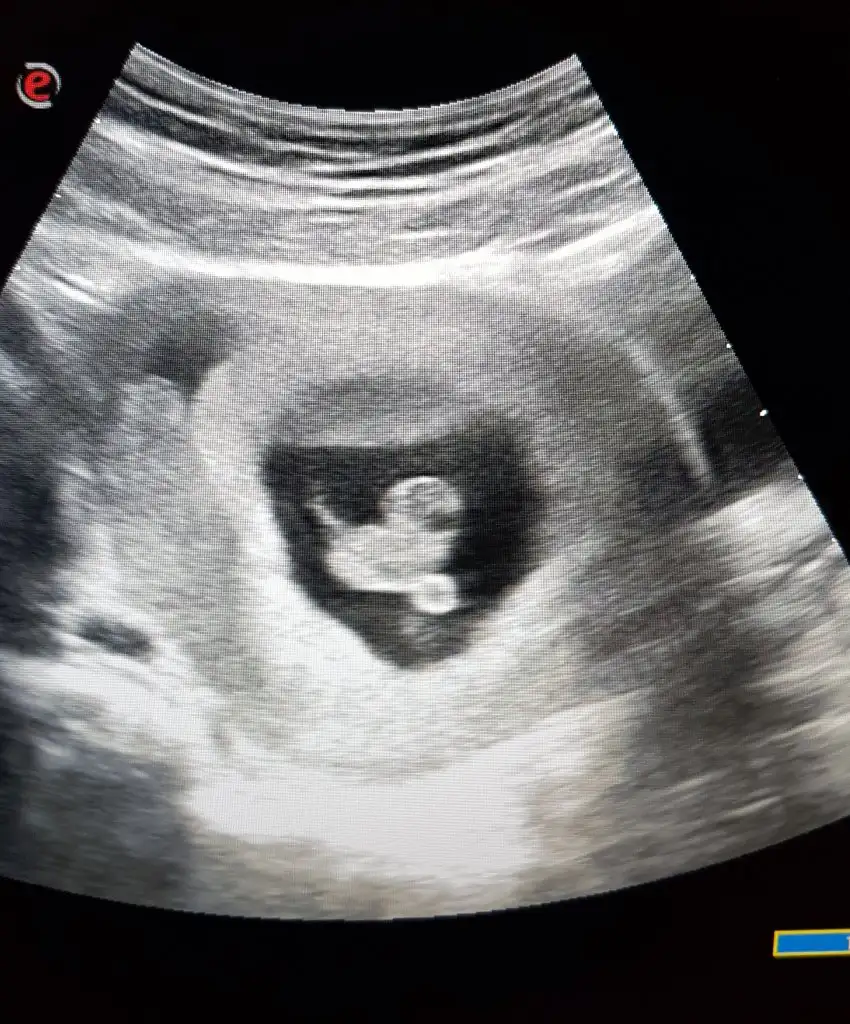

Kiza benziyo ama pek emin degilimEki Görüntüle 3073009 bizde 7 haftalığız karından tahminde bulunabilir misiniz